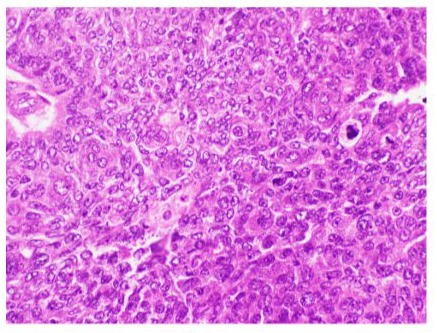

Figure 5: Microphotograph of sebaceous carcinoma showing cytoplasmic vacuoles and mitotic activity (Hematoxylin & Eosin at magnification X20).

Histopathology

In SGC patients, various clinico-pathological factors are associated with a poor prognosis of the tumor. These factors include lymphovascular and orbital invasion, involvement of both upper and lower eyelids, poor differentiation, multicentric origin, long duration of symptoms, large tumor size, an infiltrative pattern, and pagetoid invasion of the epithelium of the skin or conjunctiva. Prognosis is generally better for tumors originating from the glands of Zeis. However, tumors originating from the upper eyelids have a worse prognosis compared to those of the lower lids [2, 3].